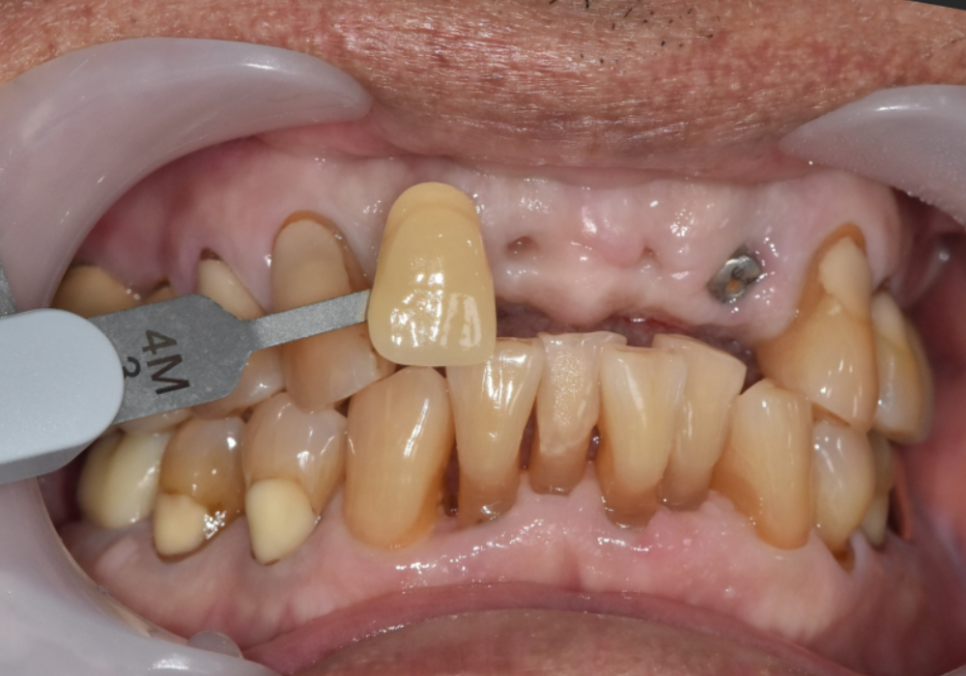

아무리 수술이 잘 되었어도

임플란트 보철이 제대로 나오지 않으면

수많은 수정 과정을 거치게 됩니다.

특히, 앞니는 보이는 부위이다 보니

보철의 색감이나 모양,

미세한 길이 차이에도

환자분들이 더 예민해질 수밖에 없습니다.

앞니 임플란트, 원내 기공소를 통해 짧은 기간에 제작 가능한 보철

"조금만 더 밝았으면 좋겠어요."

"이쪽이 살짝 어색한 것 같아요."

이런 조율이 반복되면

보철 제작 기간이 늘어지는 경우도

적지 않습니다.

저희는 원내기공소가 있기 때문에

기공사와 바로 소통하며

환자분 의견을 그때그때 반영할 수 있었고,

불필요한 재제작이나

대기 시간을 줄일 수 있었습니다.

250402

그 덕분에

앞니라는 심미적인 부담이 있는 부위임에도

치료 기간을 크게 늘리지 않고

환자분이 만족하실 만한 보철을

완성할 수 있었습니다.